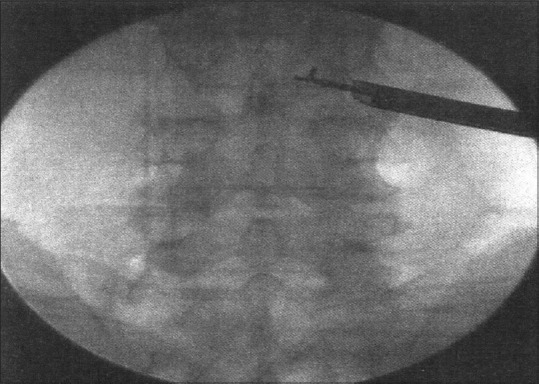

A guide wire is introduced through the needle, and the passage is dilated with the obturator that is threaded onto the guide wire till it reaches the annulus [Figure 3]. The next step was annular fenestration, in which the blunt-tapered obturator was advanced manually or with a mallet (patient is sedated before thrusting the obtuator past the annulus) [Figure 4]. A beveled working cannula is guided over the dilator to position it into the disc [Figure 5]. The next step is fragmentectomy where the decompression is done from medial to lateral aspect of the disc using rongeurs of various sizes under direct vision [Figure 6]. After decompressing the dural sac laterally to the spinous process in the AP view guided by the C-arm, the working cannula was retracted until it reached the medial pedicular line and the foramen. The decision of adequate decompression was accomplished by visual inspection of mobility of a free-floating dural sac and epidural space [Figure 7].

Figure 6.

Rongeurs inserted into the disc space through the working cannula as seen on C-arm